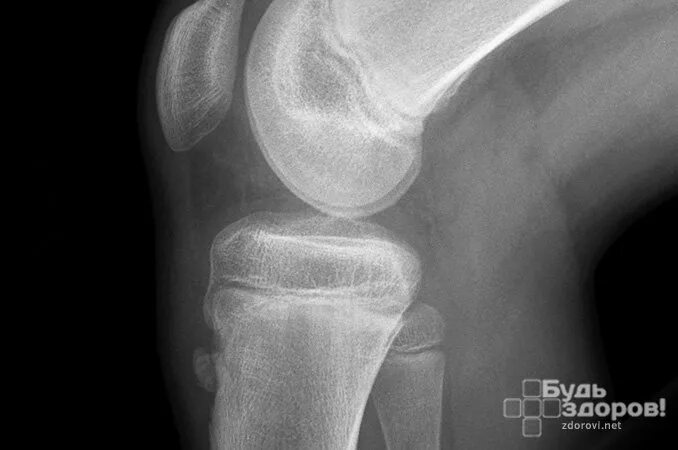

Код мкб шляттера